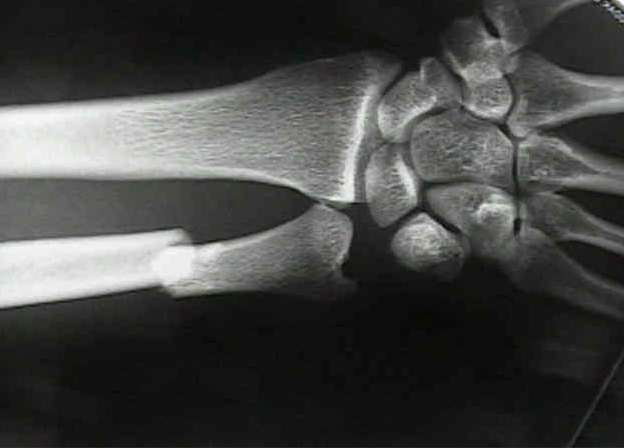

Ved hevelse, misfarging og palpasjonsømhet rundt håndleddet, samt feilstilling i dorsal og radial retning - hvilket håndleddsbrudd kan man mistenke?

Distal radiusfraktur.